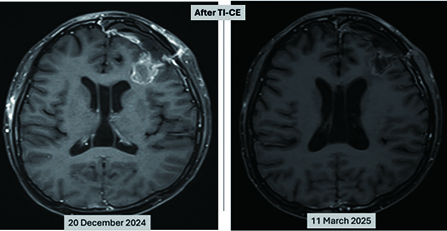

肺腺癌與乳癌治療的新曙光:別讓 HER2「基因突變」成為漏網之魚